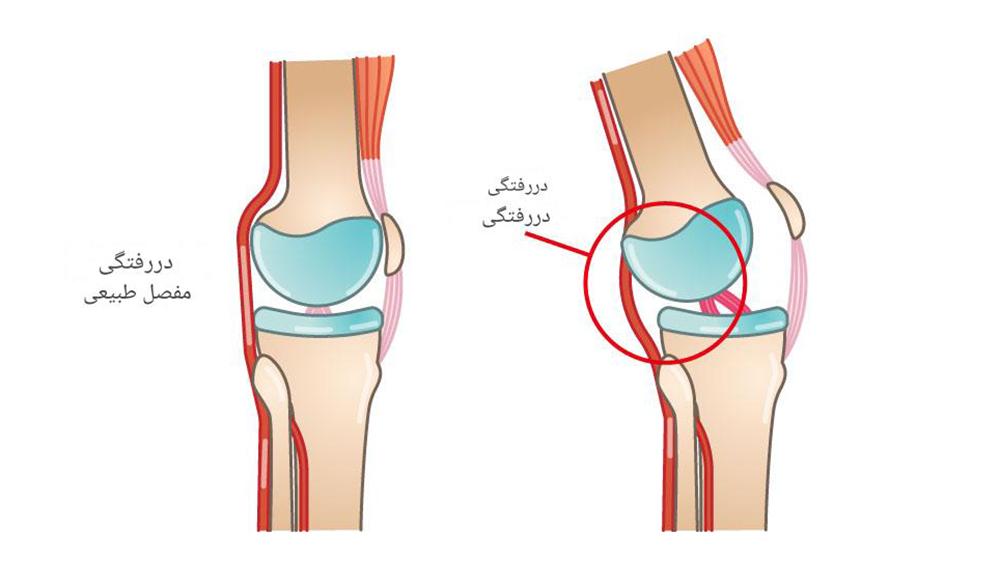

رباط ها و تاندون ها هر دو از بافت همبند فیبری تشکیل شده اند، اما شباهت در اینجا به پایان می رسد. رباط ها به صورت نوارهای متقاطع ظاهر می شوند که استخوان را به استخوان می چسبانند و به تثبیت مفاصل کمک می کنند. به عنوان مثال، رباط صلیبی قدامی (ACL) استخوان ران را به استخوان ساق پا متصل می کند و مفصل زانو را تثبیت می کند.

رباط ها و تاندون ها را می توان اینطور تعریف کرد. که رباطها را بهعنوان طناب با یک سری طنابهای سخت و در هم تنیده در نظر بگیرید که استخوانها را به هم متصل میکنند. رباط ها همچنین دارای الیاف الاستیک هستند که به مفصل اجازه حرکت می دهد، اما نه آنقدر که بیش از ظرفیت خود حرکت کند.

به عنوان مثال، مفصل زانو دارای چهار رباط اصلی است، یکی در هر طرف زانو و دو رباط که به صورت مورب در جلو و پشت کاسه زانو قرار دارند. این رباط ها به تثبیت زانو کمک می کنند و از حرکت بیش از حد به سمت چپ یا راست، جلو یا عقب جلوگیری می کنند.

هنگامی که یک رباط بیش از حد کشیده یا پاره می شود، منجر به چیزی می شود که از نظر فنی به آن رگ به رگ شدن می گویند. بسیاری از رگ به رگ شدن ها به طور ناگهانی یا در اثر زمین خوردن، حرکت نامناسب یا ضربه اتفاق می افتد.

پیچ خوردگی معمولا در مچ پا، زانو یا مچ دست اتفاق می افتد. به عنوان مثال، یک گام اشتباه می تواند باعث شود که مچ پای خود را در موقعیتی نامناسب بپیچانید، رباطی را بشکافید و باعث بی ثباتی یا لرزش مچ پا شود. ممکن است هنگام آسیب دیدگی صدای پارگی بشنوید یا احساس پارگی کنید. زمانی که دست دراز کرده خود را برای شکستن زمین دراز میکنید، مچ دست اغلب رگ به رگ میشود، فقط برای اینکه مچ دست به عقب باز شود. این افزایش کشش رباط را بیش از حد کشیده می کند.

علائم رگ به رگ شدن رباط عموماً شامل درد، تورم و کبودی در ناحیه آسیب دیده است. ممکن است مفصل شل یا ضعیف شود و نتواند وزن را تحمل کند. شدت علائم شما بسته به اینکه رباط بیش از حد کشیده شده باشد یا واقعاً پاره شده باشد، متفاوت خواهد بود.

پزشکان رگ به رگ شدن ها را بر اساس درجات طبقه بندی می کنند، از درجه 1 (پیچ خوردگی خفیف با کشیدگی جزئی رباط) تا درجه 3 (پارگی کامل رباط که باعث ناپایداری مفصل می شود).